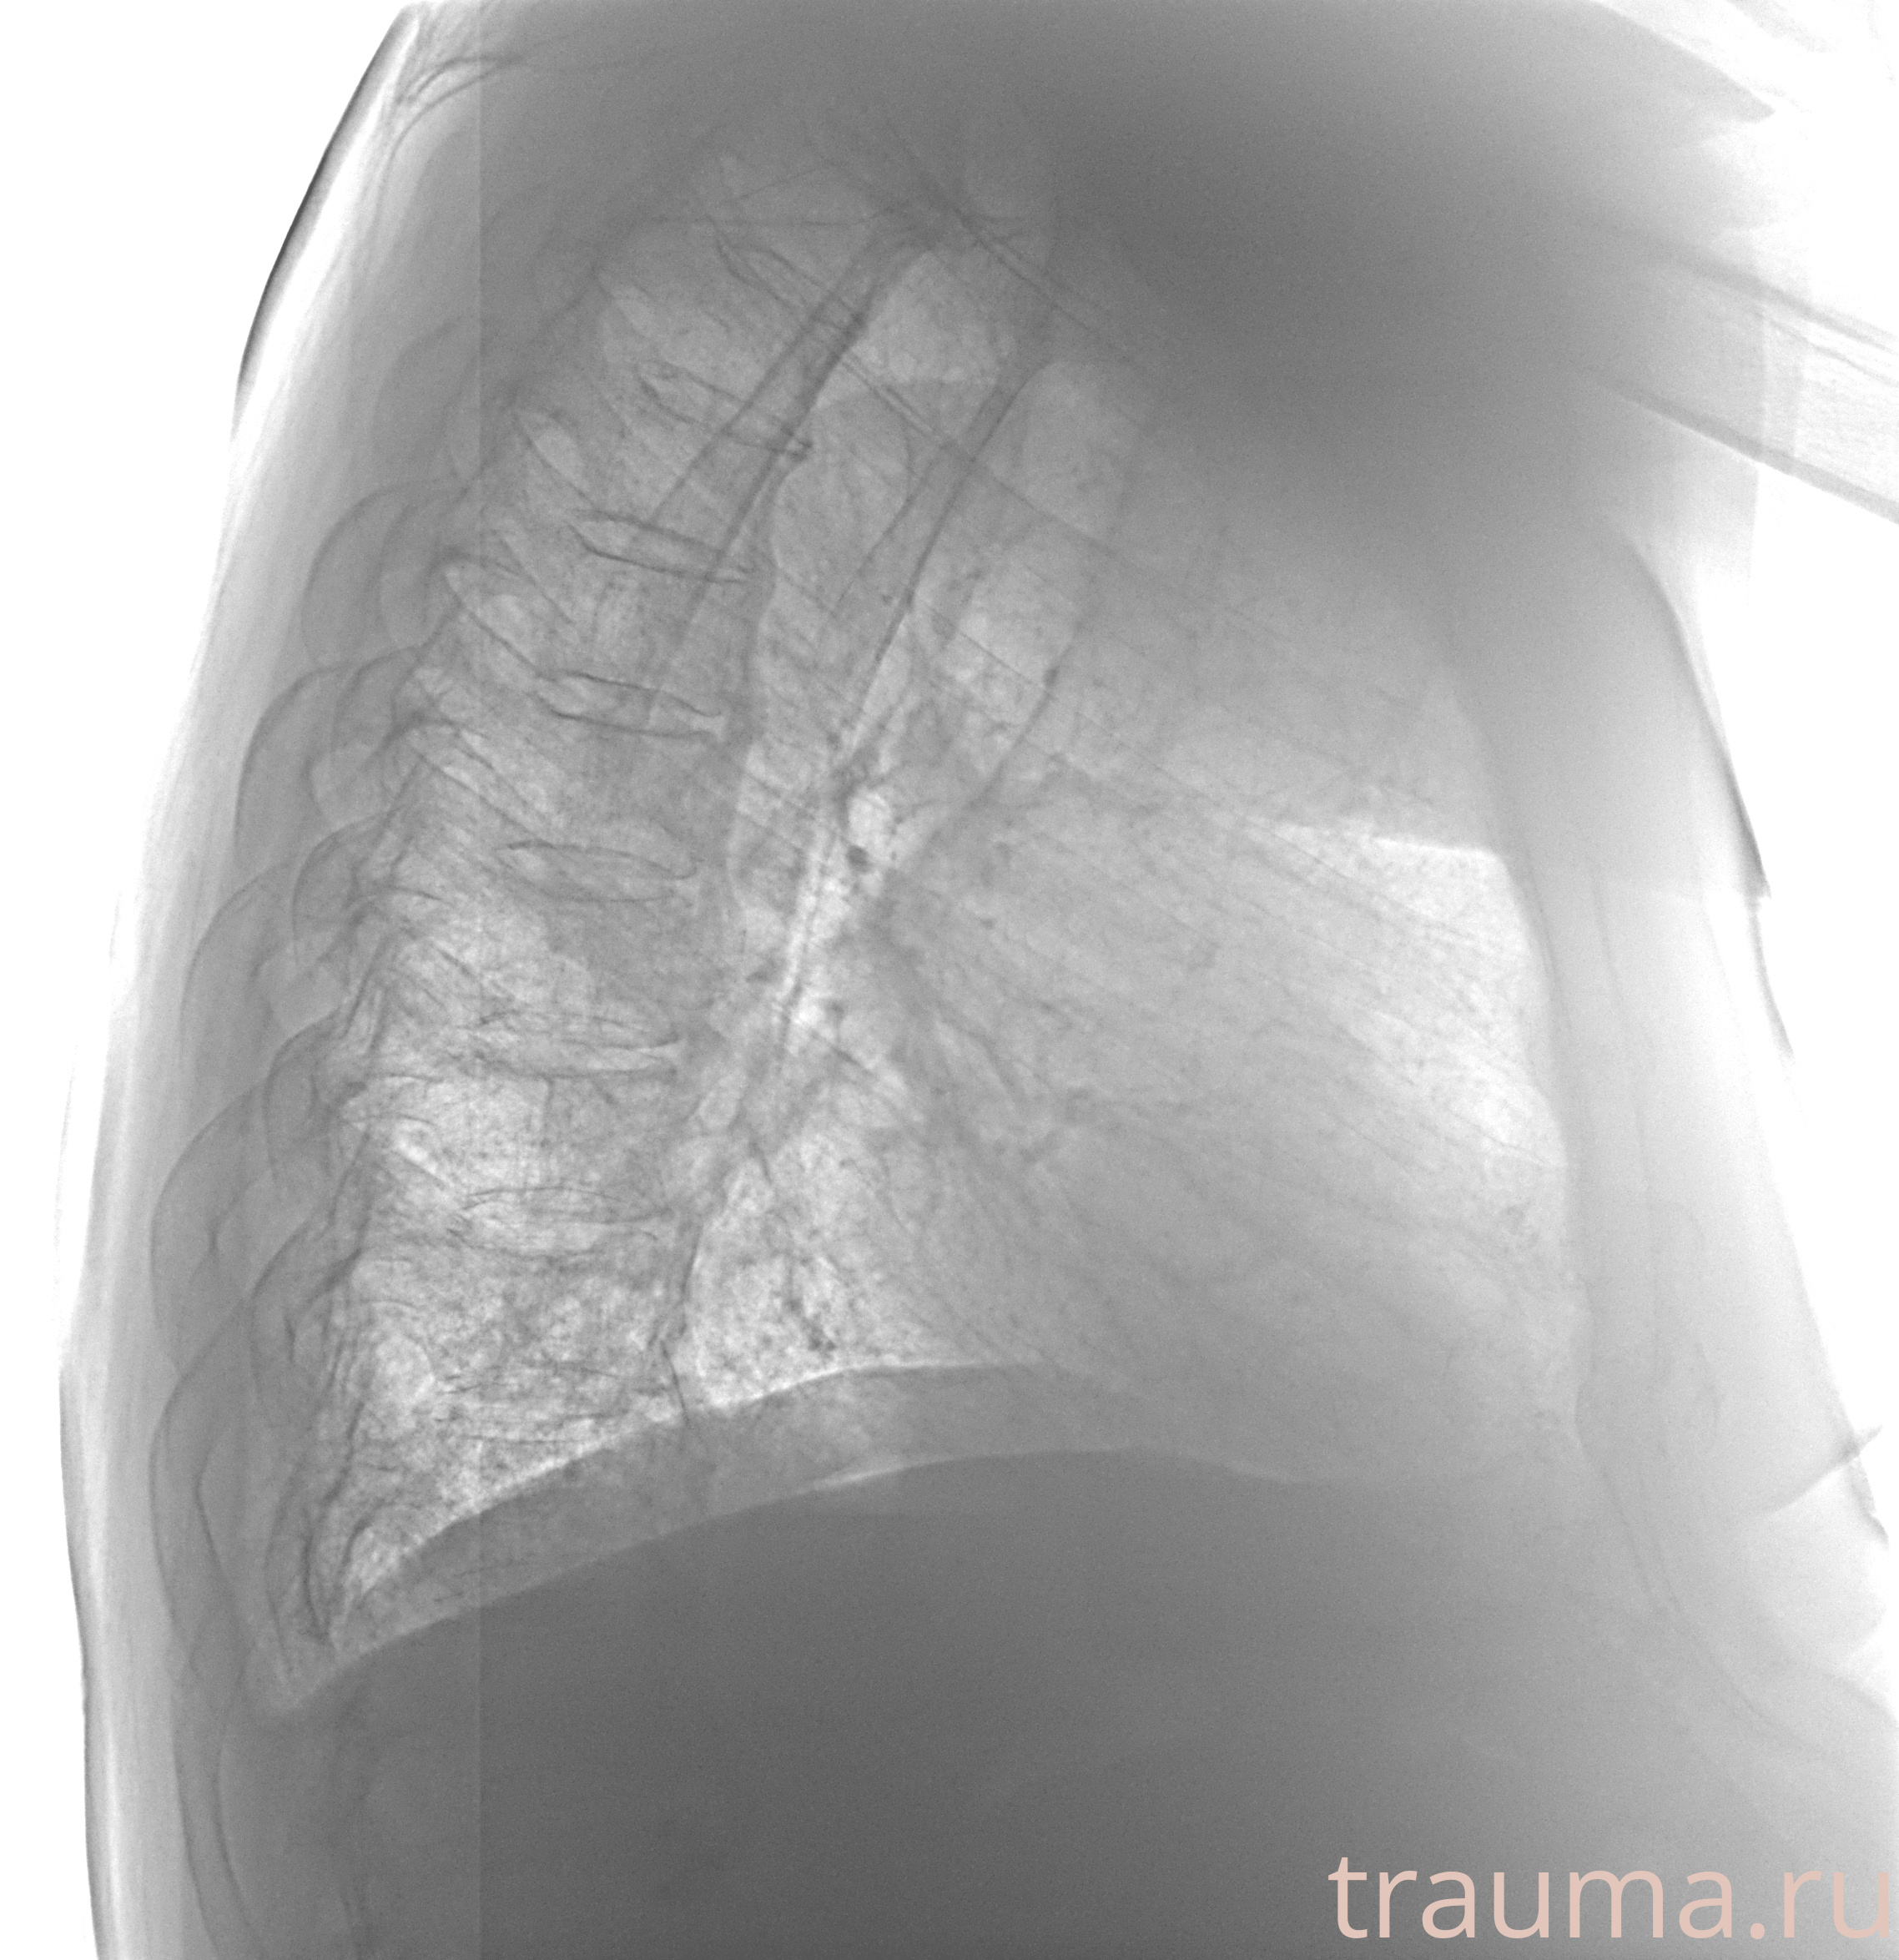

Рентген на дому: по вашему адресу приезжает врач-рентгенолог, травматолог-ортопед с мобильным рентгеновским аппаратом, проводит диагностику травмы или заболевания, делает необходимые рентгенограммы, дает рекомендации по дальнейшему лечению. Получить качественные снимки в домашних условиях возможно благодаря уникальной методике, разработанной МосРентген Центром для института  Склифосовского